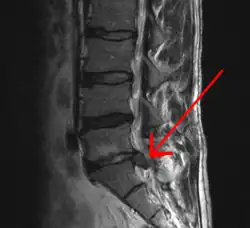

A herniated disc as seen on MRI, one possible cause of low back pain

The straight leg raise test can detect pain originating from a herniated disc. When warranted, imaging such as MRI can provide clear detail about disc related causes of back pain (L4–L5 disc herniation shown).

Imaging is indicated when there are red flags, ongoing neurological symptoms that do not resolve, or ongoing or worsening pain.[5] In particular, early use of imaging (either MRI or CT) is recommended for suspected cancer, infection, or cauda equina syndrome.[5] MRI is slightly better than CT for identifying disc disease; the two technologies are equally useful for diagnosing spinal stenosis.[5] Only a few physical diagnostic tests are helpful.[5] The straight leg raise test is almost always positive in those with disc herniation,[5] and lumbar provocative discography may be useful to identify a specific disc causing pain in those with chronic high levels of low back pain.[47] Therapeutic procedures such as nerve blocks can also be used to determine a specific source of pain.[5] Some evidence supports the use of facet joint injections, transforminal epidural injections and sacroiliac injections as diagnostic tests.[5] Most other physical tests, such as evaluating for scoliosis, muscle weakness or wasting, and impaired reflexes, are of little use.[5]